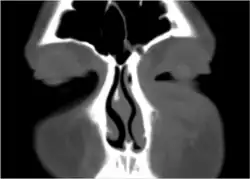

If the diagnosis is unclear, a CT scan may be done to rule out other possibilities.

- Periorbital cellulitis caused by a dental infection (also causing maxillary sinusitis)